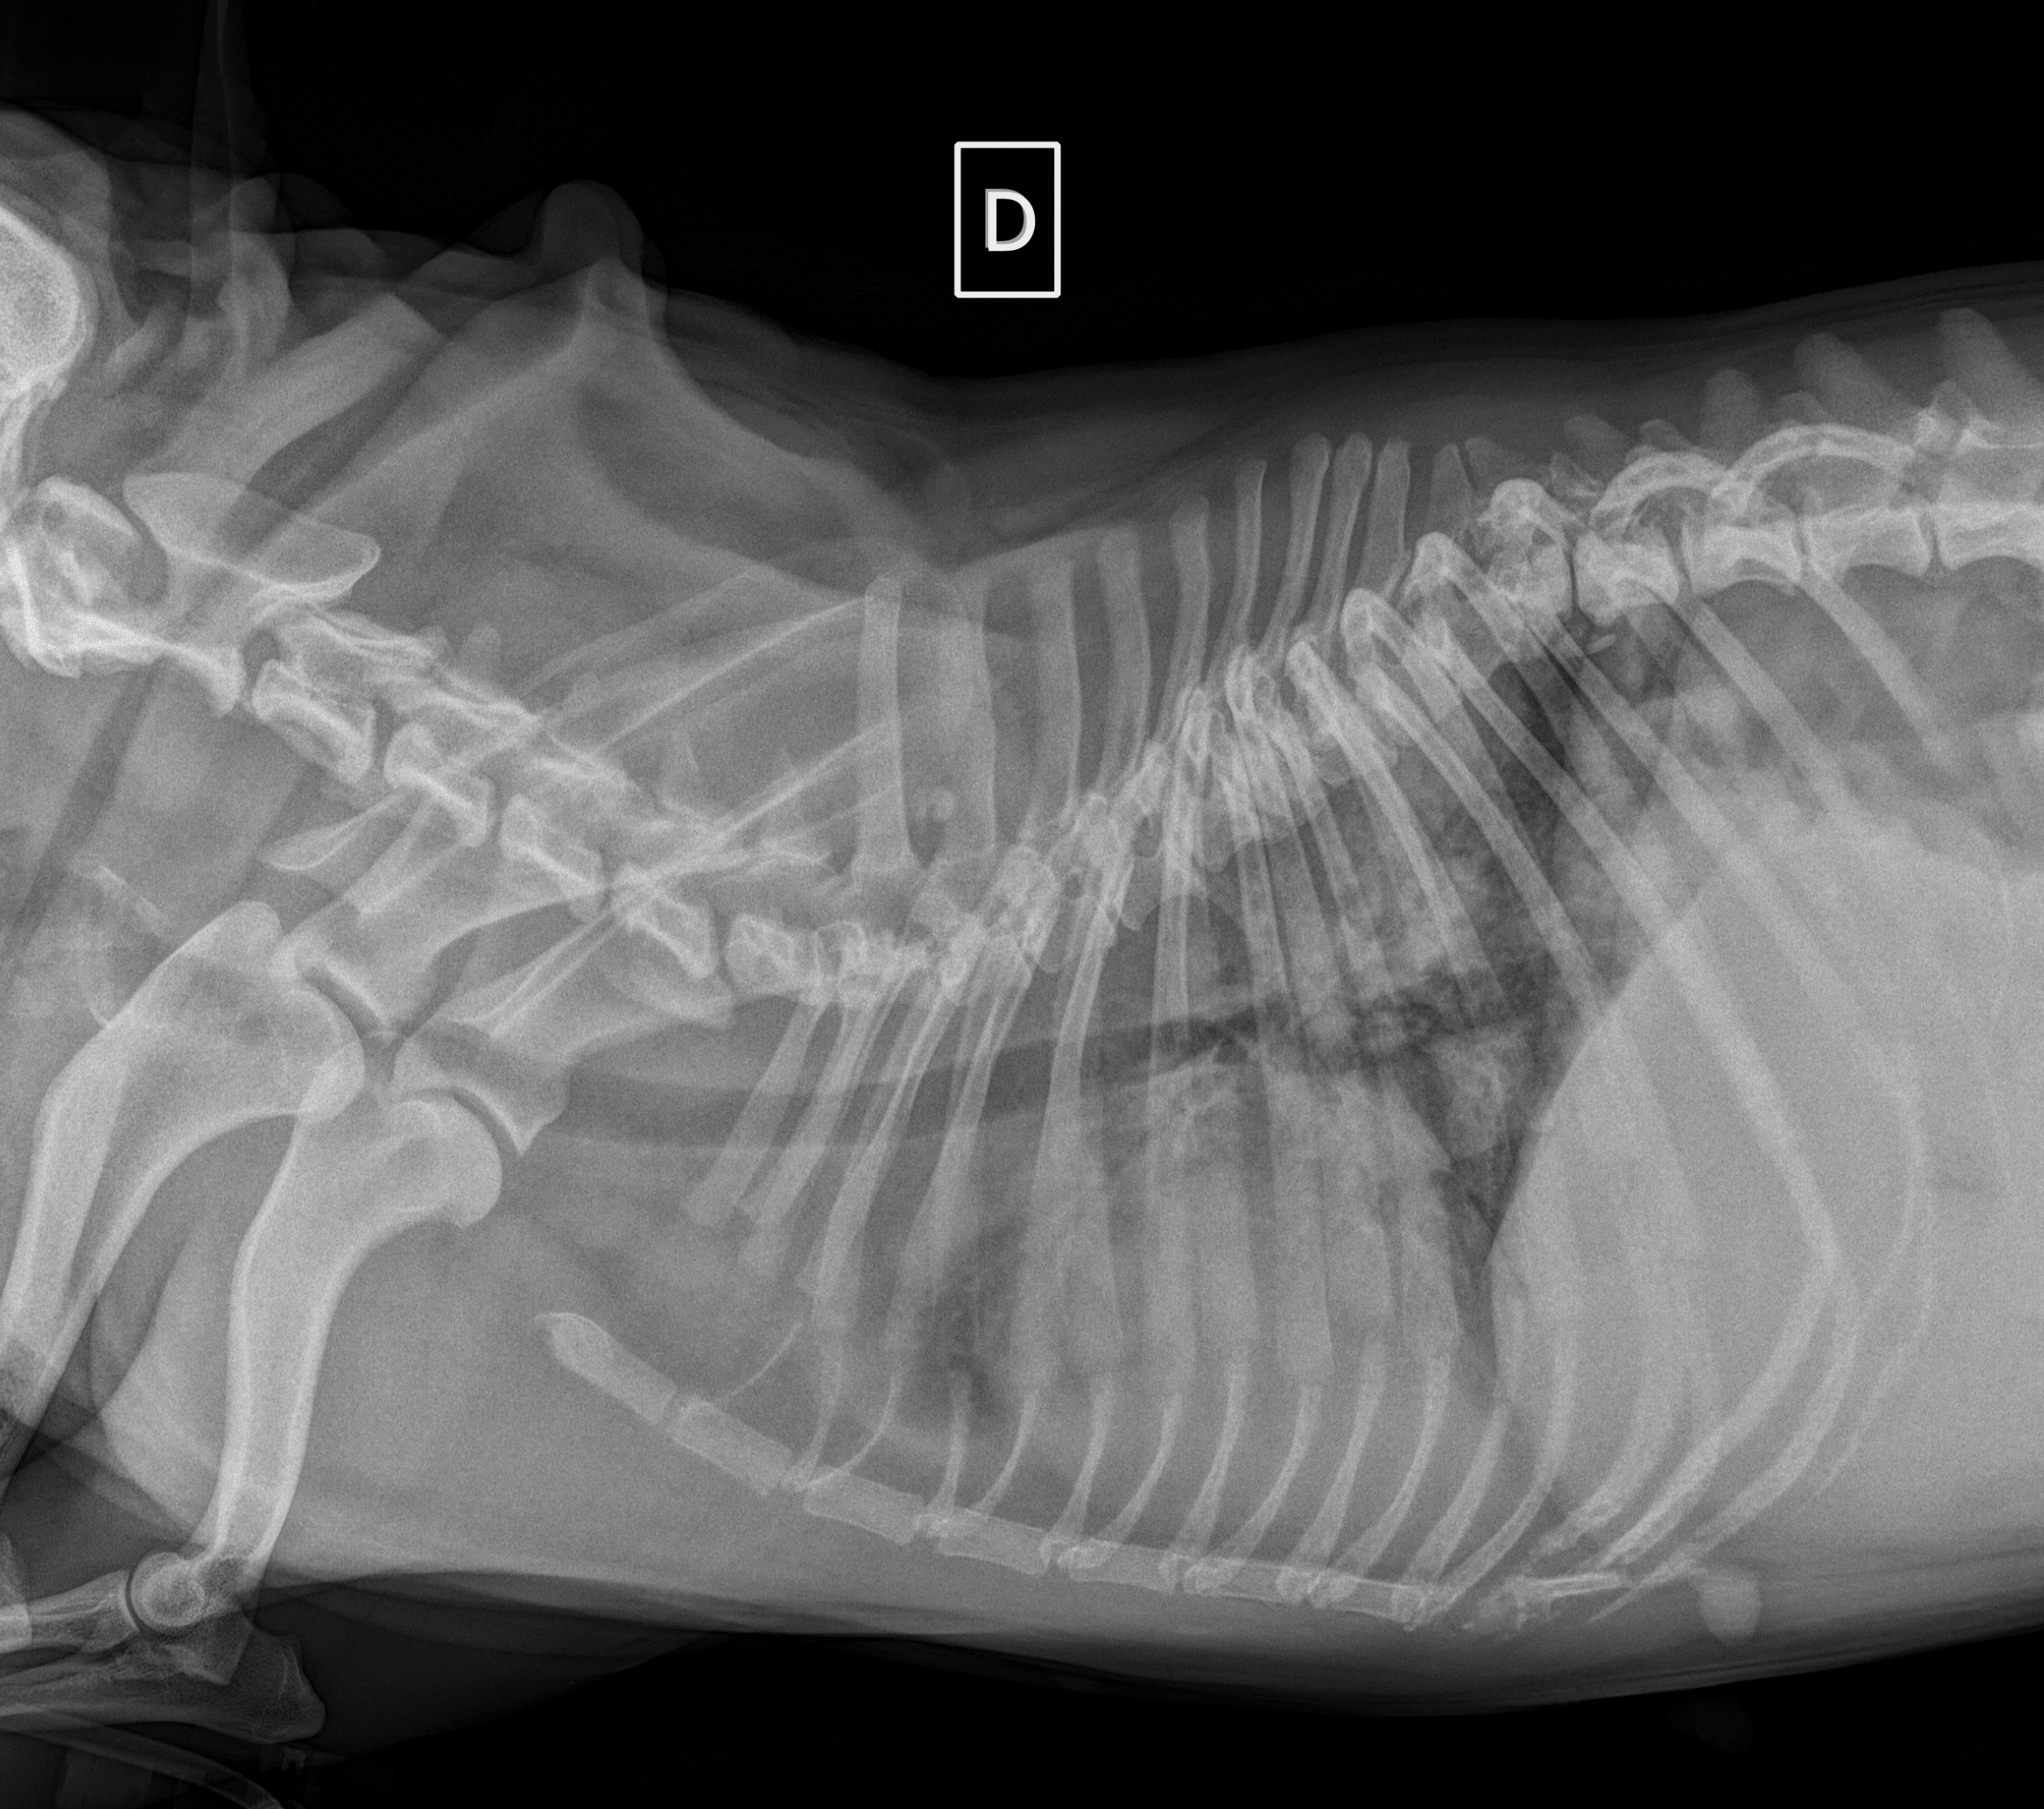

Leptospirose chez le chien